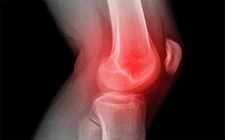

Diz kapağı ameliyatı, diz ekleminde meydana gelen çeşitli rahatsızlıkların tedavisinde uygulanan cerrahi bir müdahaledir. Bu tür ameliyatlar, genellikle diz kapağının yerinden çıkması, yaralanmalar, artrit veya diğer diz problemleri nedeniyle gerçekleştirilir. Ancak, bu tür bir cerrahinin kendi içinde belirli riskler ve sonrasında göz önünde bulundurulması gereken durumlar söz konusudur. Diz Kapağı Ameliyatının RiskleriDiz kapağı ameliyatı, her cerrahi işlemde olduğu gibi bazı riskler taşır. Bu riskler arasında şunlar yer almaktadır: